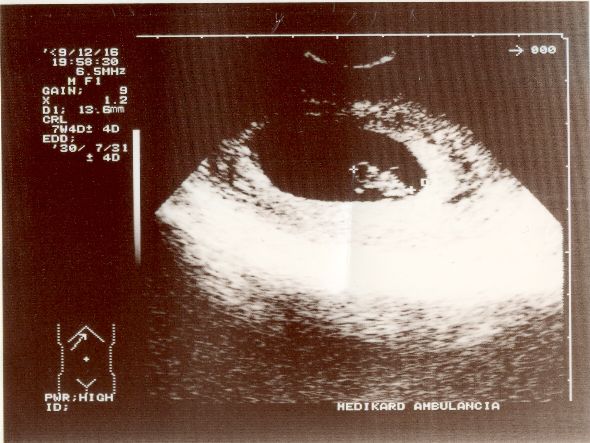

Amúgy pénteken töltöttem a 8 hetet, hivatalosan is 2010 július 28.-ra vagyok kiírva és akkor Bajcsyban fogok szülni..

Itt 7 hetes és 5 napos! Múlt szerdai kép.